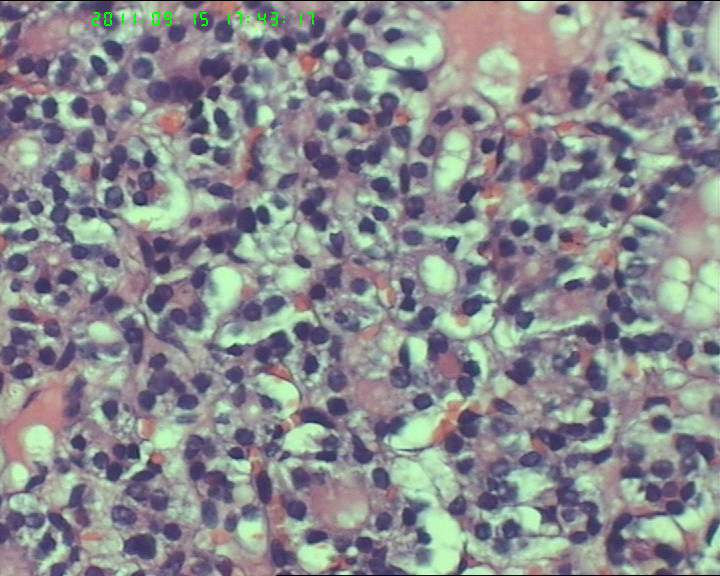

甲状腺右下极一肿物,3*3大小,切面灰红实性质韧,可见部分包膜,一侧可见一空腔,未见内容物。

38岁女性甲状腺,腺瘤?滤泡癌?图2

名称:图2

描述:20110915-2.jpg.jpg

够不够滤泡癌,要找有没有浸润。网友们,这么多图片,有包膜浸润吗(哪几张是包膜)?图12、14又是什么?

如找不到明确的胞膜,血管浸润和正常甲状腺组织破坏,最好诊断非典型腺瘤.

非典型腺瘤,没有看到明显的血管浸润及包膜浸润